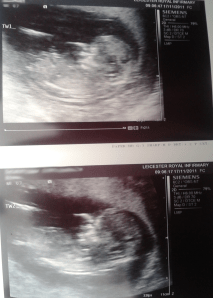

The babies are not so recent a development; I learned about them the weekend I returned from my last LARP last year. Of course we decided to keep it quiet until that all important three month marker, but it was still on my mind, you know? Now its all about twins and moses baskets and birth plans and pain management. >.< Even more interesting because more than before, the pregnancy is starting to take its toll on my day to day life.

I’m pregnant. With twins. They are due on 26 May, though in all likeliness I’ll go in three weeks early for an inducement – something that my consultant told me, very early on was what might be best. Of course, that’s on the assumption that my precious babes don’t decide that they would like to breathe the free air a little sooner than that. Who can tell, right? I have no idea what they are, other than to say that they’re identical and will therefore be either two boys or two girls. Originally I quite liked the idea of one of each, though two of one ‘flavour’ if you like, is growing on me a great deal. If only because I can imagine playing all sorts of tricks on people when they’re old enough to play along with me. Heh, and then, of course, when they’re old enough to play tricks on me I’ll have be sure that I’m wise to it.